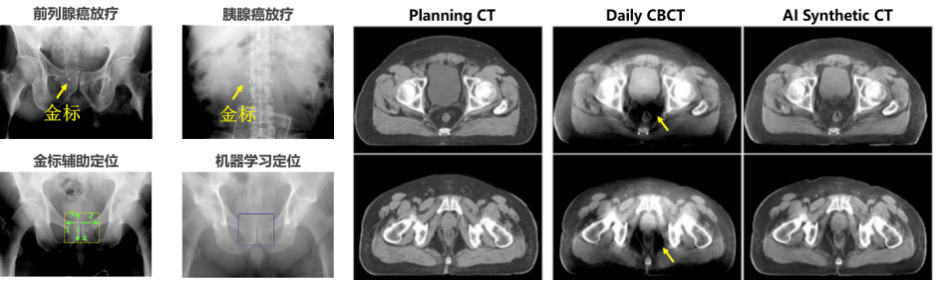

l 图像引导放射治疗